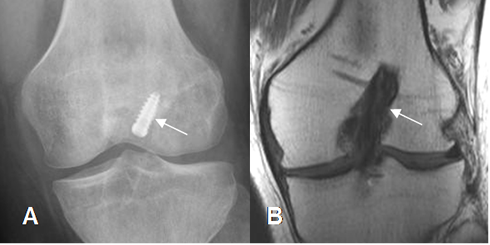

Fig 130. Túnel femoral normal.

A: Rx lateral y B: RM sagital en T1. Orientación normal del túnel femoral, en la parte posterior del cóndilo femoral.

Fig 131. Túnel femoral normal.

A: Rx AP y B: RM coronal en T1. Orientación normal del túnel femoral, dirigido hacia la 1, de las manecillas del reloj.